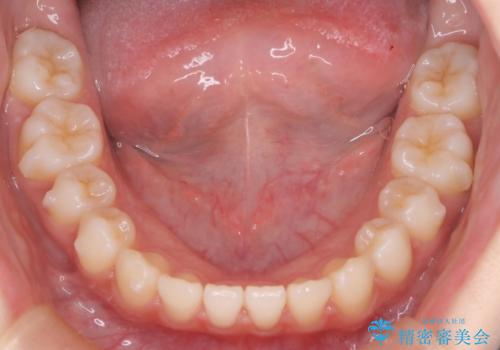

見た目、嚙み合わせ及び、治療期間や施術内容に大変ご満足いただきました。